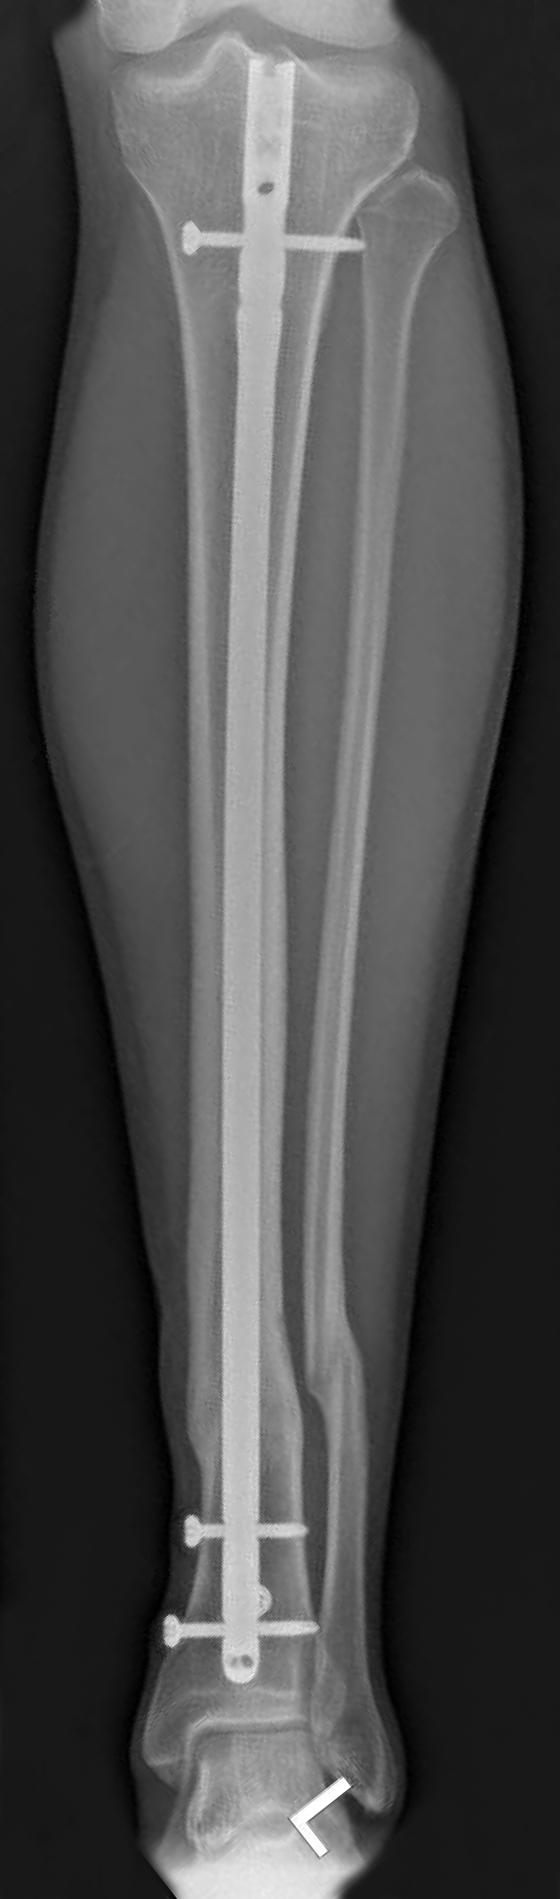

Figuur 5.

Verschillende operatieve opties voor de behandeling van fracturen van het onderbeen met: A. platen en schroeven; B. pen die geplaatst is in de mergholte van het scheenbeen.